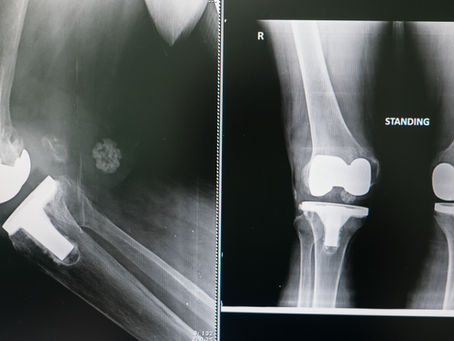

Tratamientos de Cartílago vs Prótesis de Rodilla

¿Por qué cambia la recomendación antes y después de los 50 años? Cuando aparece dolor de rodilla por desgaste o lesión del cartílago, muchos pacientes se preguntan: “¿Me conviene reparar el cartílago o de plano ponerme una prótesis?” La respuesta depende en gran parte de la edad, del estado del cartílago y de la calidad del hueso. 1. ¿Por qué es tan importante la edad en la reparación del cartílago? El cartílago articular no tiene vasos sanguíneos, lo que significa que su cap